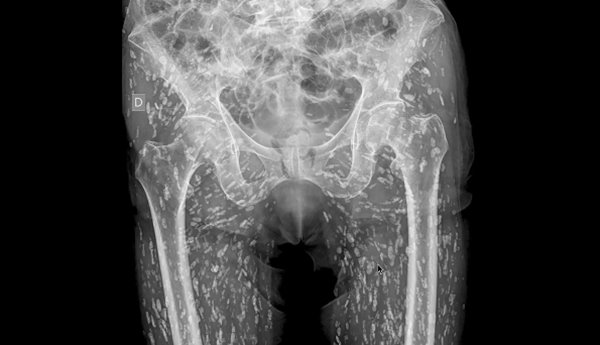

หมอเผยภาพเอกซเรย์ชวนสยดสยอง สีขาว ๆ ที่เห็นคือความสะพรึง มีมาถึงต้นขา เกิดจากอะไร เตือนสิ่งที่ไม่ควรทำ

วันที่ 21 มกราคม 2568 เว็บไซต์อ็อดดิตี้เซ็นทรัล เผยว่า เมื่อเร็ว ๆ นี้ มีแพทย์ห้องฉุกเฉินรายหนึ่ง ได้เผยภาพเอกซเรย์ที่น่าตกตะลึง โดยเขาระบุว่าเป็น "ภาพเอกซเรย์ที่บ้าที่สุดเท่าที่เขาเคยเห็นมา" เมื่อแสดงให้เห็นว่าภายในร่างกายส่วนล่างของผู้ป่วยเต็มไปด้วยจุดสีขาวเล็ก ๆ มากมายเกินกว่าร้อยจุด กระจายอยู่ทั่วบริเวณตัวมาจนถึงที่ต้นขา โดยจุดสีขาวที่เห็นในภาพเอกซเรย์นี้ก็คือ ไข่ของพยาธิตัวตืดที่กลายเป็นหินปูน

ดร.แซม กาลี แพทย์ประจำแผนก ER ผู้เชี่ยวชาญด้านภาวะฉุกเฉินทางหัวใจและหลอดเลือดและรังสีวิทยาฉุกเฉิน ในสหรัฐอเมริกา ได้แชร์ภาพเอกซเรย์บริเวณอุ้งเชิงกรานของผู้ป่วยรายหนึ่ง ซึ่งได้เข้ามาขอรับการรักษา ภาพหลังจากประสบอุบัติเหตุล้มและมีอาการปวดสะโพก โดยที่เขาไม่เคยล่วงรู้มาก่อนเลยว่า มีไข่พยาธิตัวตืดที่กลายเป็นหินปูน ซ่อนอยู่ในตัวของเขาเป็นจำนวนมากมายเช่นนี้ และเขาก็ไม่เคยรู้เรื่องเกี่ยวกับพยาธิตัวตืดมาก่อนด้วยเช่นกัน

พยาธิตัวตืดเป็นปรสิตที่มักจะเกาะติดอยู่ภายในลำไส้เพื่อดูดซับสารอาหาร แต่ไข่พยาธิตัวตืดยังสามารถเดินทางไปได้ทุกที่ภายในร่างกาย ตั้งแต่เท้าไปจนถึงสมอง เมื่อเวลาผ่านไป ไข่พยาธิตัวตืดเหล่านี้จะกลายเป็นหินปูน และไม่สามารถดำรงชีวิตได้อีกต่อไป หากไข่พยาธิตัวตืดเข้าไปเกาะในเนื้อเยื่ออ่อน เช่น กล้ามเนื้อหรือไขมัน ก็อาจจะไม่เป็นภัยคุกคามถึงชีวิต แต่หากขึ้นไปที่สมอง ก็สามารถทำให้เกิดภาวะที่เป็นอันตรายถึงชีวิตได้

ดร.แซม อธิบายสถานการณ์ในภาพเอกซเรย์ดังกล่าว ระบุว่า "สิ่งนี้เรียกว่า โรคถุงพยาธิตืดหมู (Cysticercosis) เป็นโรคที่เกิดจากตัวอ่อนของพยาธิตืดหมูไปฝังตัวตามอวัยวะต่าง ๆ ของร่างกายคน และสามารถแพร่กระจายไปทั่วร่างกายได้ โดยส่วนใหญ่ไปอยู่ที่กล้ามเนื้อและเนื้อเยื่ออ่อนบริเวณสะโพกและขา"